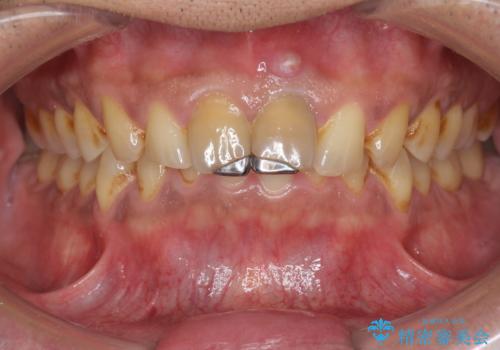

- 体調により前歯部の歯ぐきから出血や膿が出ることの改善を求めて来院されました。

X線写真より、根尖部に透過像が認められ根管治療・ファイバーコア築盛・セラミッククラウンの作製が必要な状態です。